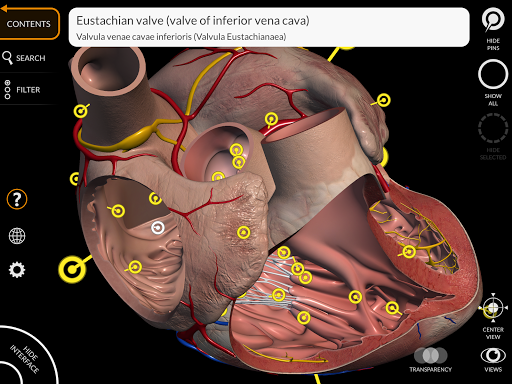

"Anatomy 3D Atlas" vous permet d'étudier l'anatomie humaine de manière simple et interactive.

Grâce à une interface simple et intuitive, il est possible d'observer chaque structure anatomique sous n'importe quel angle.

Les modèles anatomiques 3D sont particulièrement détaillés et avec des textures jusqu'à une résolution de 4k.

La subdivision par régions et les vues prédéfinies facilitent l'observation et l'étude de parties individuelles ou de groupes de systèmes et les relations entre différents organes.

MODÈLES ANATOMIQUES 3D

• Système cardiovasculaire

• En sélectionnant un modèle ou une épingle, le terme anatomique associé apparaît